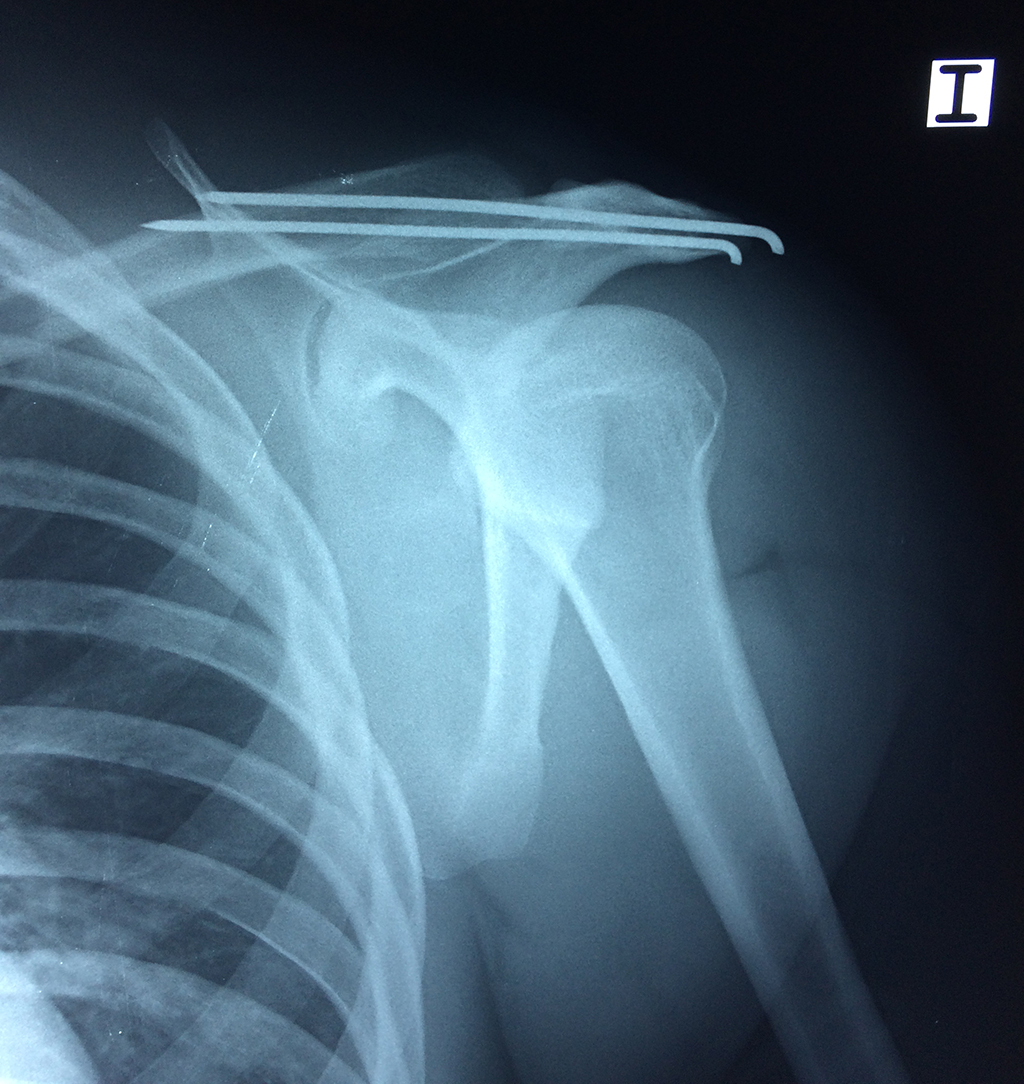

En anatomía humana, el hombro es la parte del cuerpo donde se une el brazo con el tronco. Está formado por la conjunción de los extremos de tres huesos: la clavícula, la escápula y el húmero; así como por músculos, ligamentos y tendones.

La principal articulación del hombro es la que une la cabeza del húmero con la escápula, recibe el nombre de articulación escapulohumeral y presenta dos superficies articulares, una de ellas corresponde a la cabeza del humero que tiene forma semiesférica y la otra es la cavidad glenoidea de la escápula, estas superficies están recubiertos por cartílago que permiten un movimiento suave e indoloro.